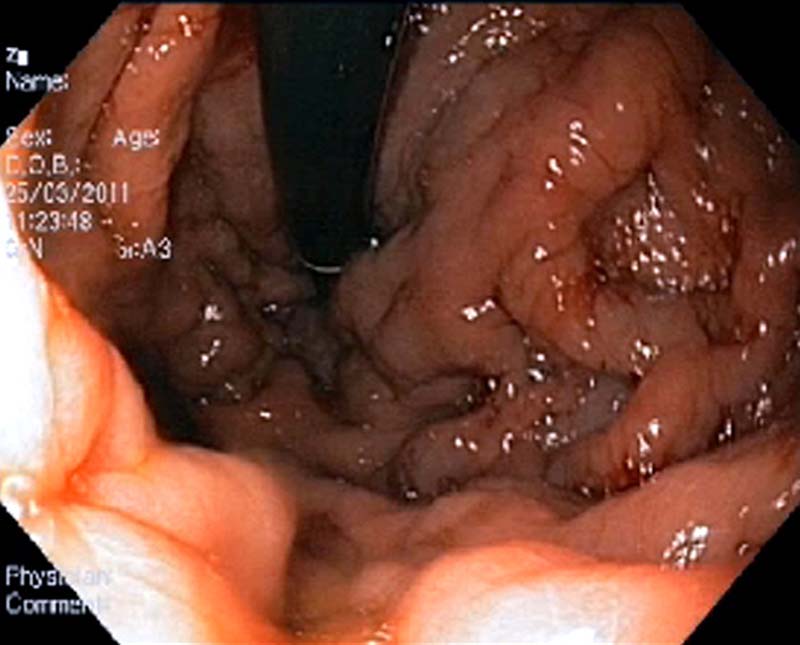

Наряду с неспецифическими проявлениями, важными клиническими симптомами являются спленомегалия (нередко достигающая гигантских размеров), а также симптомы анемии и/или гипербилирубинемии (при их наличии). [20] Набор инструментальных методов исследования, так же как и в случае ОТВВ, включает в себя УЗДГ, КТ или МР-ангиографию, ЭГДС. Последняя обнаруживает ВРВ пищевода и желудка, при этом они часто имеют большой диаметр и распространяются на весь пищевод (рис. 2), начиная от его верхней трети; переходят на кардию, тело и дно желудка (рис. 3). [6, 7, 10, 13, 14, 25, 44, 50] Наличие эктопических ВРВ (в двенадцатиперстной кишке, аноректальной зоне, ложе желчного пузыря) более характерно для данной группы пациентов, чем для больных ЦП. [53, 54]

Рис. 2. Эндоскопическая картина ВРВ пищевода при тромбозе воротной вены.